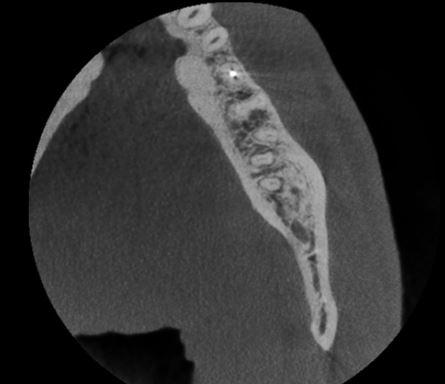

Reconstructed panoramic view and cross sections showing the

relationship of the mesial root apex of the LL8 to the IDN.